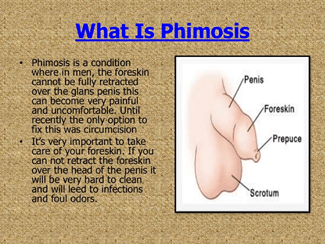

Phimosis is a condition in which the prepuce cannot be retracted over the glans penis. It could be further defined as physiologic, as in infancy and childhood, or pathologic. Pathologic phimosis would result from inflammatory or traumatic injury to the prepuce resulting in an acquired inelastic scar that prevents retraction. Forceful disruption of physiologic adhesions in infants no doubt encourages pathologic phimosis. Physiologic phimosis is common in male patients up to 3 years of age, but often extends into older age groups.